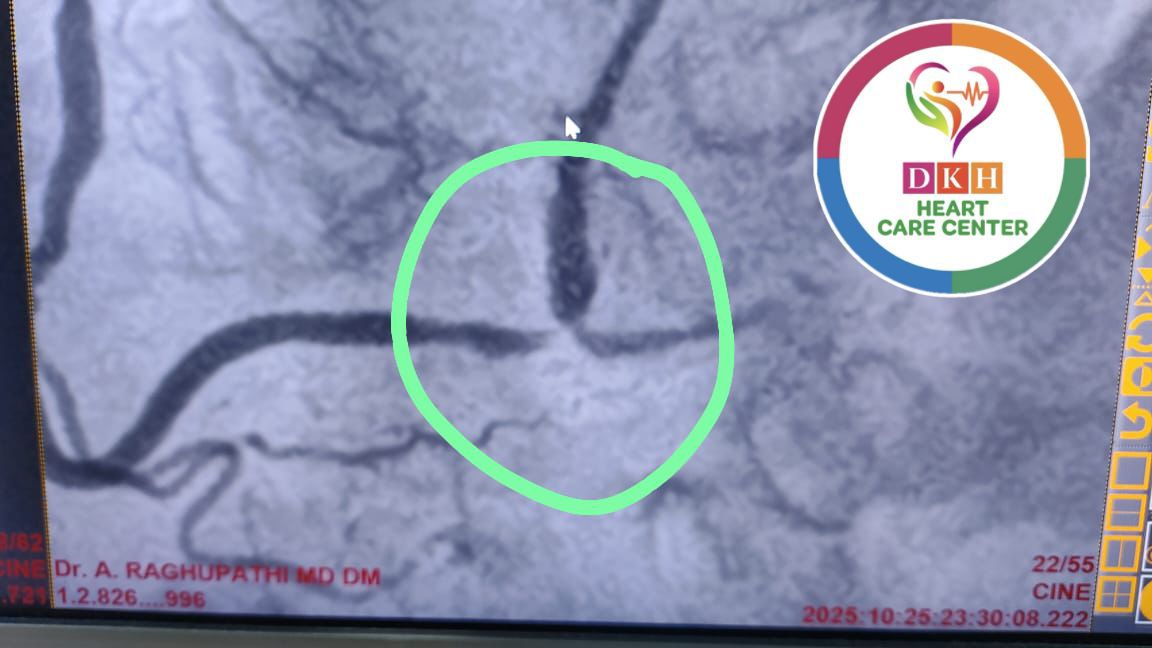

Deepa Kannan Hospital Heart Care Center & Cath Lab stands as a beacon of excellence in cardiovascular medicine. With state-of-the-art catheterization laboratory facilities and a team of renowned cardiac specialists, we are committed to providing comprehensive heart care services that combine cutting-edge technology with personalized patient care.

State-of-the-art cardiac catheterization laboratory with advanced imaging technology